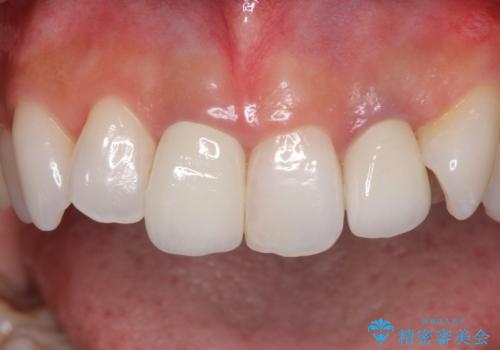

2歯をオールセラミッククラウン(ジルコニアクラウン)にて補綴することとしました。

土台の金属はグラスファイバーを含有したものに、クラウンの土台は強化セラミックとすることで、自然な前歯に仕上がりました。